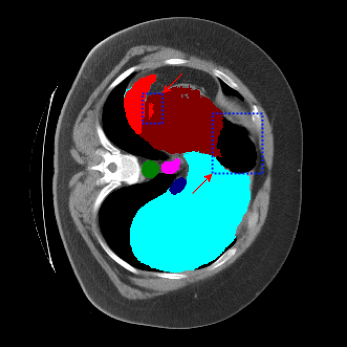

| Ground Truth | LoGoNet | DiNTS Search |

|---|---|---|

![]() |

We begin by qualitatively inspecting our model. Figure 3 compares the output of LoGoNet to the best performing baseline model in BTCV dataset, i.e., DiNTS Search (more qualitative comparisons can be found in appendix section 11). We see that our model particularly excels in segmenting organ boundaries. This can be attributed to our effective strategy for extracting local-range dependencies, which plays a crucial role in extracting details from input data. Our model’s adeptness in capturing long-range dependencies allows it to grasp contextual information that extends over significant distances within the data. Simultaneously, its proficiency in handling short-range dependencies ensures precision in capturing localized patterns.